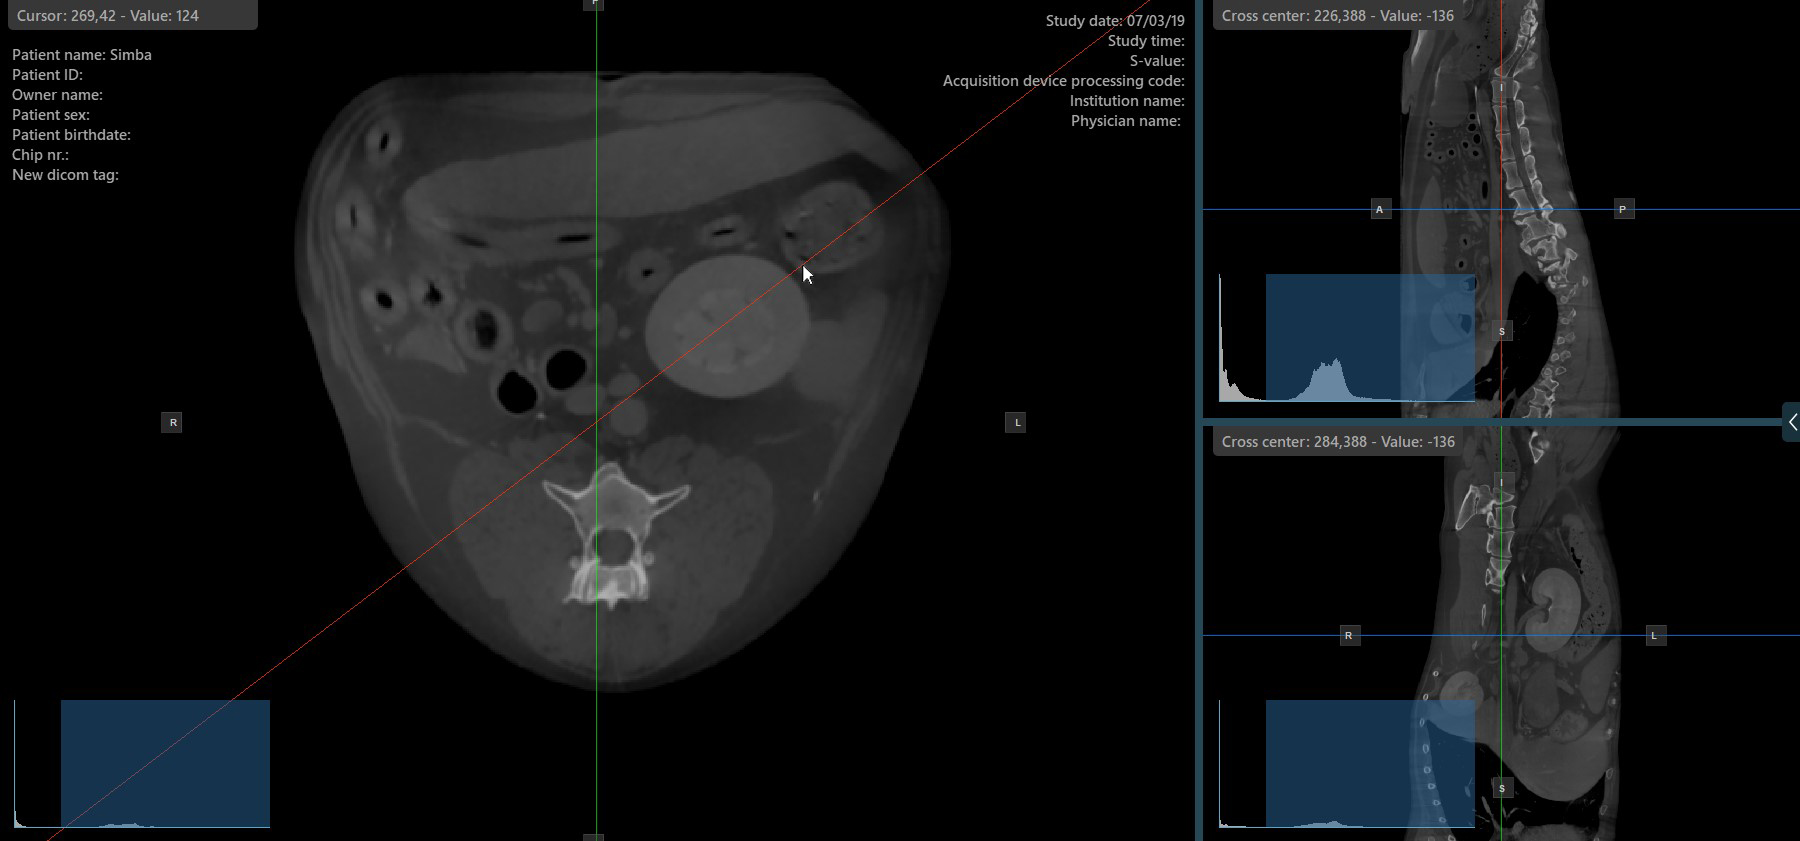

The slicers in MPR view show the intersections and orientation of the three image planes displayed in the active viewports. Users can modify the slicers and change the cross-sectional position of the slices based on the 3D volumetric data.

Each slicers is distinguished by their specific color, which representes the image plane:

The blue slicer marks the axial plane of the object (perpendicular to the ground)

The red slicer marks the coronal plane (parallel to the ground)

The green slicer marks the sagittal plane (perpendicular to the body)

Altering the rotation of a slicer will change the orientation of the corresponding image planes. Individual slicers can be selected by using the Select Item (Default)

tool, assigned to the right mouse button by default.

Once the specific slicer is selected, drag the slicer in the desired direction to rotate it. The corresponding image plane’s orientation changes accordingly.